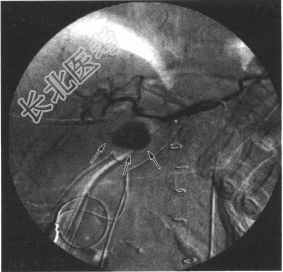

- 多项选择题11.该患者急诊腹腔动脉血管造影见下图。该患者的诊断是( )

A、肝右动脉假性动脉瘤破裂出血

B、肝固有动脉破裂出血

C、肝总动脉假性动脉瘤破裂出血

D、胃十二指肠动脉假性动脉瘤破裂出血

E、肠系膜上动脉破裂出血

F、腹腔动脉破裂出血